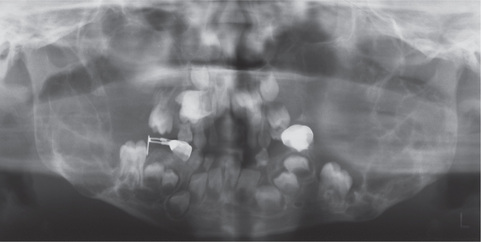

Fibrous dysplasia of the maxilla is an especially serious form of the disease since it has a marked predilection for occurrence in children and is almost impossible to eradicate without radical, mutilating surgery (Fig. 17-8). These lesions are not well circumscribed, commonly extend locally to involve the maxillary sinus, the zygomatic process and the floor of the orbit, and even extend back toward the base of the skull. Severe malocclusion and bulging of the canine fossa or extreme prominence of the zygomatic process, producing a marked facial deformity, are typical sequelae of this disease in this location need not be truly monostotic, but neither is it usually classified as a polyostotic type. It has sometimes been referred to as craniofacial fibrous dysplasia, since it does affect the craniofacial complex and is so characteristic in its clinical and radiographic features that it closely resembles a distinct entity (Fig. 17-9). This form of the disease has been described in detail by Waldron and Giansanti and by Eversole and his associates.